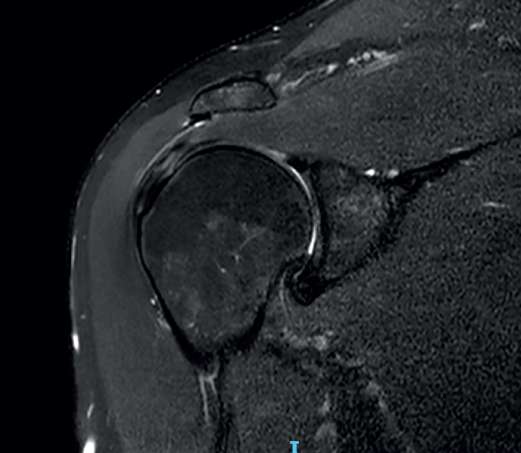

Figure 6. Severe supraspinatus tendinopathy in T2-weighted imaging.

The characteristic MRI image of tendinosis consists of a focal or intra-substance zone of intermediate signal intensity in T1-weighted imaging which does not disappear in T2 sequencing and does not reach fluid signal intensity in T2-weighted imaging (Figure 6). We can sometimes observe diffuse or focal thickening of the tendon, without evidence of rupture(33). Tendinosis may prove difficult to distinguish from early-stage partial rupture of the tendon.

Figure 7. Supraspinatus bursal partial thickness rupture in magnetic resonance imaging scan.

A lesion is classified as being of partial thickness if an abnormal fluid signal intensity in T2 sequencing is seen to extend through a portion of the tendon without affecting its full thickness (Figure 7). These may be bursal or articular lesions, though the latter are more common. There is a possibility that the thickness of the partial lesion may be occupied by scar or granulation tissue, thereby complicating the diagnosis. It has been suggested that the use of arthroMRI in the ABER (abduction + external rotation) position can improve the diagnosis and the typing of these injuries(34). According to Ellman(35), partial thickness lesions can be classified into three grades: grade I (lesion depth < 3 mm), grade II (depth 3-6 mm) and grade III (depth > 6 mm). Taking into account that a healthy supraspinatus measures between 10-12 mm in thickness, grade II lesions affect over 50% of this thickness. Intra-substance lesions are characterized by a fluid-type signal in the thickness of the tendon, without extending to the bursa or joint space.